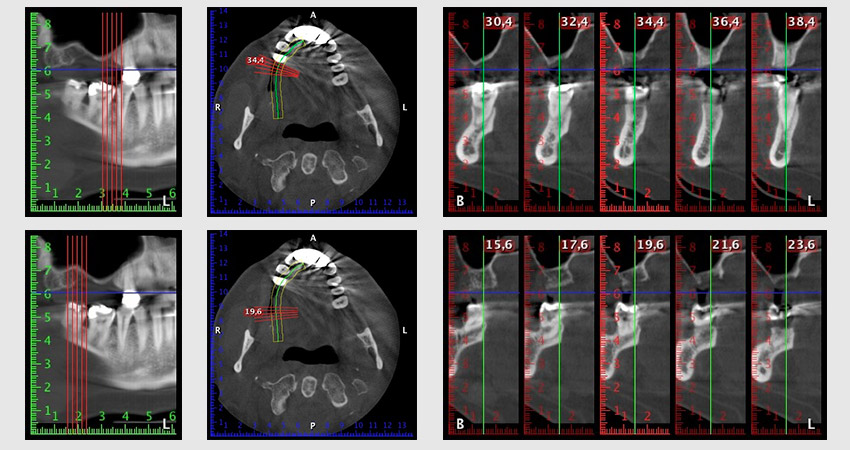

Etwa sechs Monate nach Extraktion der Zähne 16 und 14 wurde zur Planung und Risikominimierung eine digitale Volumentomografie (DVT, Planmeca) erstellt. Hierbei wurde deutlich, dass der Knochen sich nicht in der gewünschten Quantität regeneriert hat (Abb. 2 bis 7).

Abb. 2 bis 7: DVT mit stark reduziertem horizontalen Knochenangebot.

Um eine festsitzende Versorgung auf mindestens zwei Implantaten zu gewährleisten, ist eine Sinusbodenelevation sowohl in Regio 16 als auch in Regio 14 erforderlich. Da in diesem Fall das Restknochenangebot extrem gering ist, müsste ein verhältnismäßig großer Knochenaufbau durchgeführt werden. Große Knochenaufbauverfahren sind invasiv, mit einer höheren Patientenmorbidität verbunden, zeitintensiv und kostspielig. Die Vorhersagbarkeit der Behandlungsresultate ist geringer und das Misserfolgsrisiko höher. Vor dem Hintergrund dieser Nachteile, wurde die Patientin über eine herausnehmbare Alternative aufgeklärt, die sie jedoch konsequent ablehnte.

Um die Augmentation auf Regio 14 einzuschränken, wurde in Absprache mit der Patientin eine Schrägstellung des Implantats 16 nach dorso-kranial geplant (Abb. 8).